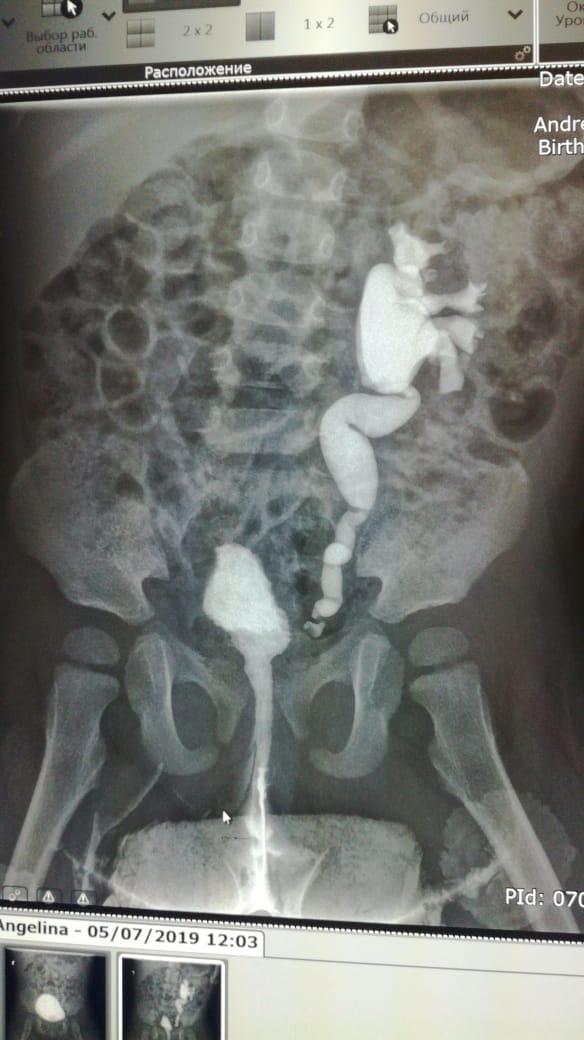

ПМР 4 степени

Здравствуйте.Моему ребенку 14.09.17г.р.была сделана вторая эндоскопическая коррекция ПМР 4 ст. в академии педиатрии СПб 07.06.19,(хотя рекомендовали и квоту одобрили на сложную операцию).08.06.19нас выписали.11.06.19г. ОАМ -удельный вес 1.006; лейкоциты 500(654,9); бактерии 13117,9;мочиться стала ещё реже 3 раза в день.17.06.19 были на приеме у нефролога,кот.нас направил обратно к урологам Академии педиатрии.Зав.отд.,посмотрев ОАМ и выписку ,спросил что я от него хочу...что ОАМ ещё ни о чем не говорит.Назначил прием Фурагина 3 раза в день по 50 мг в теч.месяца.А Вы как считаете,что лучше при такой степени рефлюкса,если почки уже страдают.